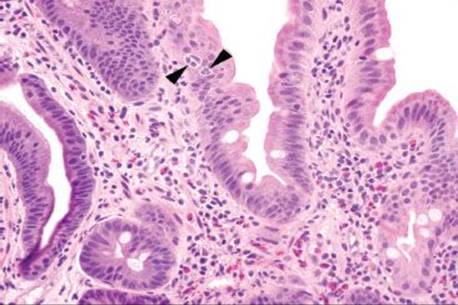

Figure 3.317 Isosporiasis. On higher power, a slight prominence of lamina propria eosinophils serves as a red flag to the diagnosis. Arrowheads highlight the Isospora organisms, which are obligate intracellular parasites and are found in the paranuclear or subnuclear cytoplasm.

Figure 3.318 Isosporiasis. On higher power, the Isospora organisms (arrowheads) are seen embedded within the epithelium. Unless the epithelial compartment is diligently inspected in every biopsy, these organisms would almost certainly be missed.

Isosporiasis is among the more common protozoan causes of severe diarrhea in AIDS patients (Figs. 3.316–3.318).190 The Isospora belli organisms are spread via contaminated water or fecal–oral contamination. They localize to the small bowel surface and are exceedingly easy to miss owing to sometimes unremarkable background mucosa and sparsely distributed organisms (Figs. 3.316–3.321). Diagnostic confirmation is facilitated through identification of the oocysts in stool samples or duodenal aspirates.191 Standard therapy consists of trimethoprim–sulfamethoxazole, which is often long term in severely immunocompromised patients.